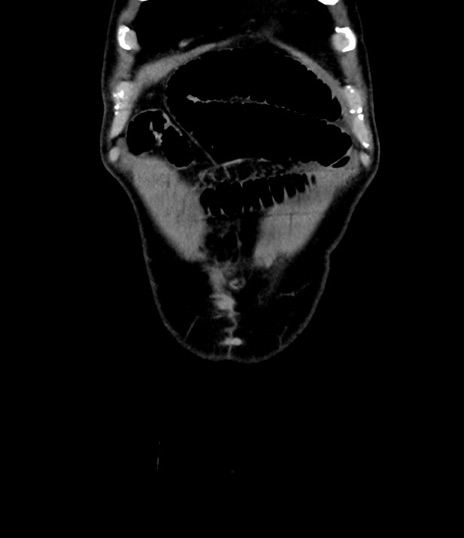

横断像